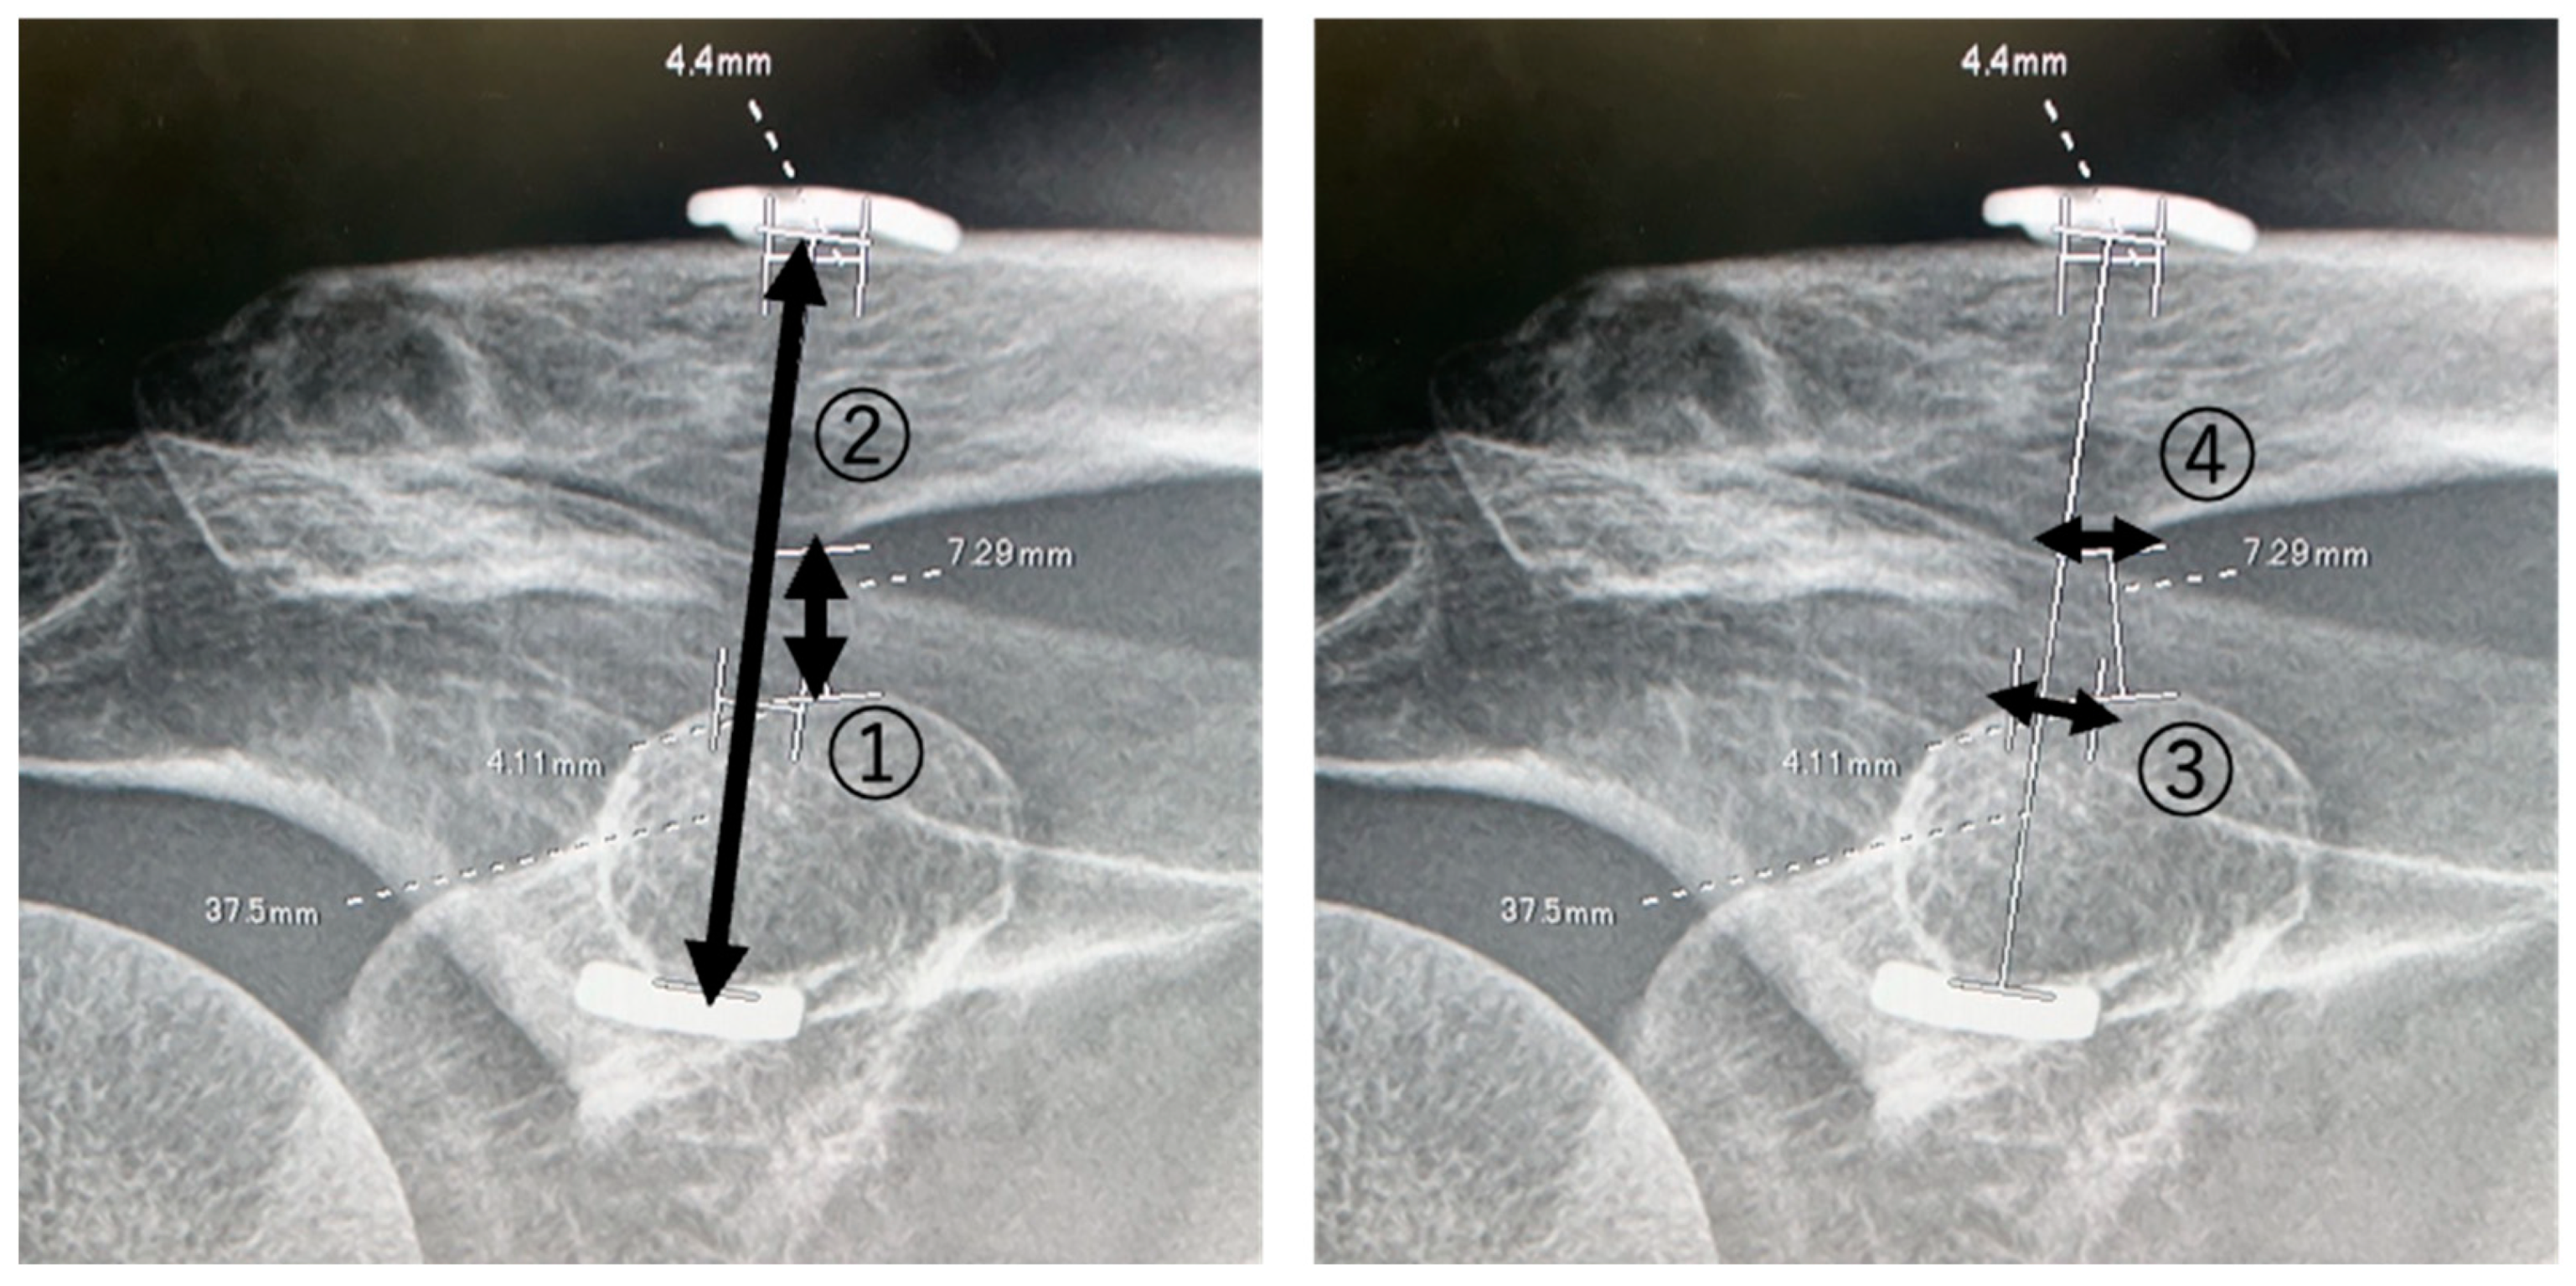

Standard anteroposterior and axial clavicle X-rays were taken systematically. Bone union, CC displacement, and bone hole sizes were assessed. Clavicular displacement was evaluated by measuring both the CC distance and the Dog Bone distance (Figure 1). Bone hole sizes were measured on the superficial side of the coracoid process and inferior side of the clavicle in the axial position immediately after surgery and at 3, 6, 9, and 12 months after surgery (Figure 1).

Figure 1. Measurements of the CC distance, Dog Bone distance, and bone holes on the superior coracoid and inferior clavicle. ①: CC distance; ②: Dog Bone distance; ③: superior coracoid bone hole; ④: inferior clavicle bone hole.